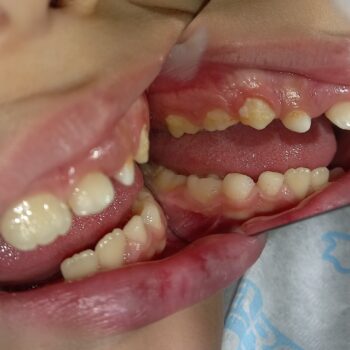

• Διάφορα περιστατικά παιδοδοντίας